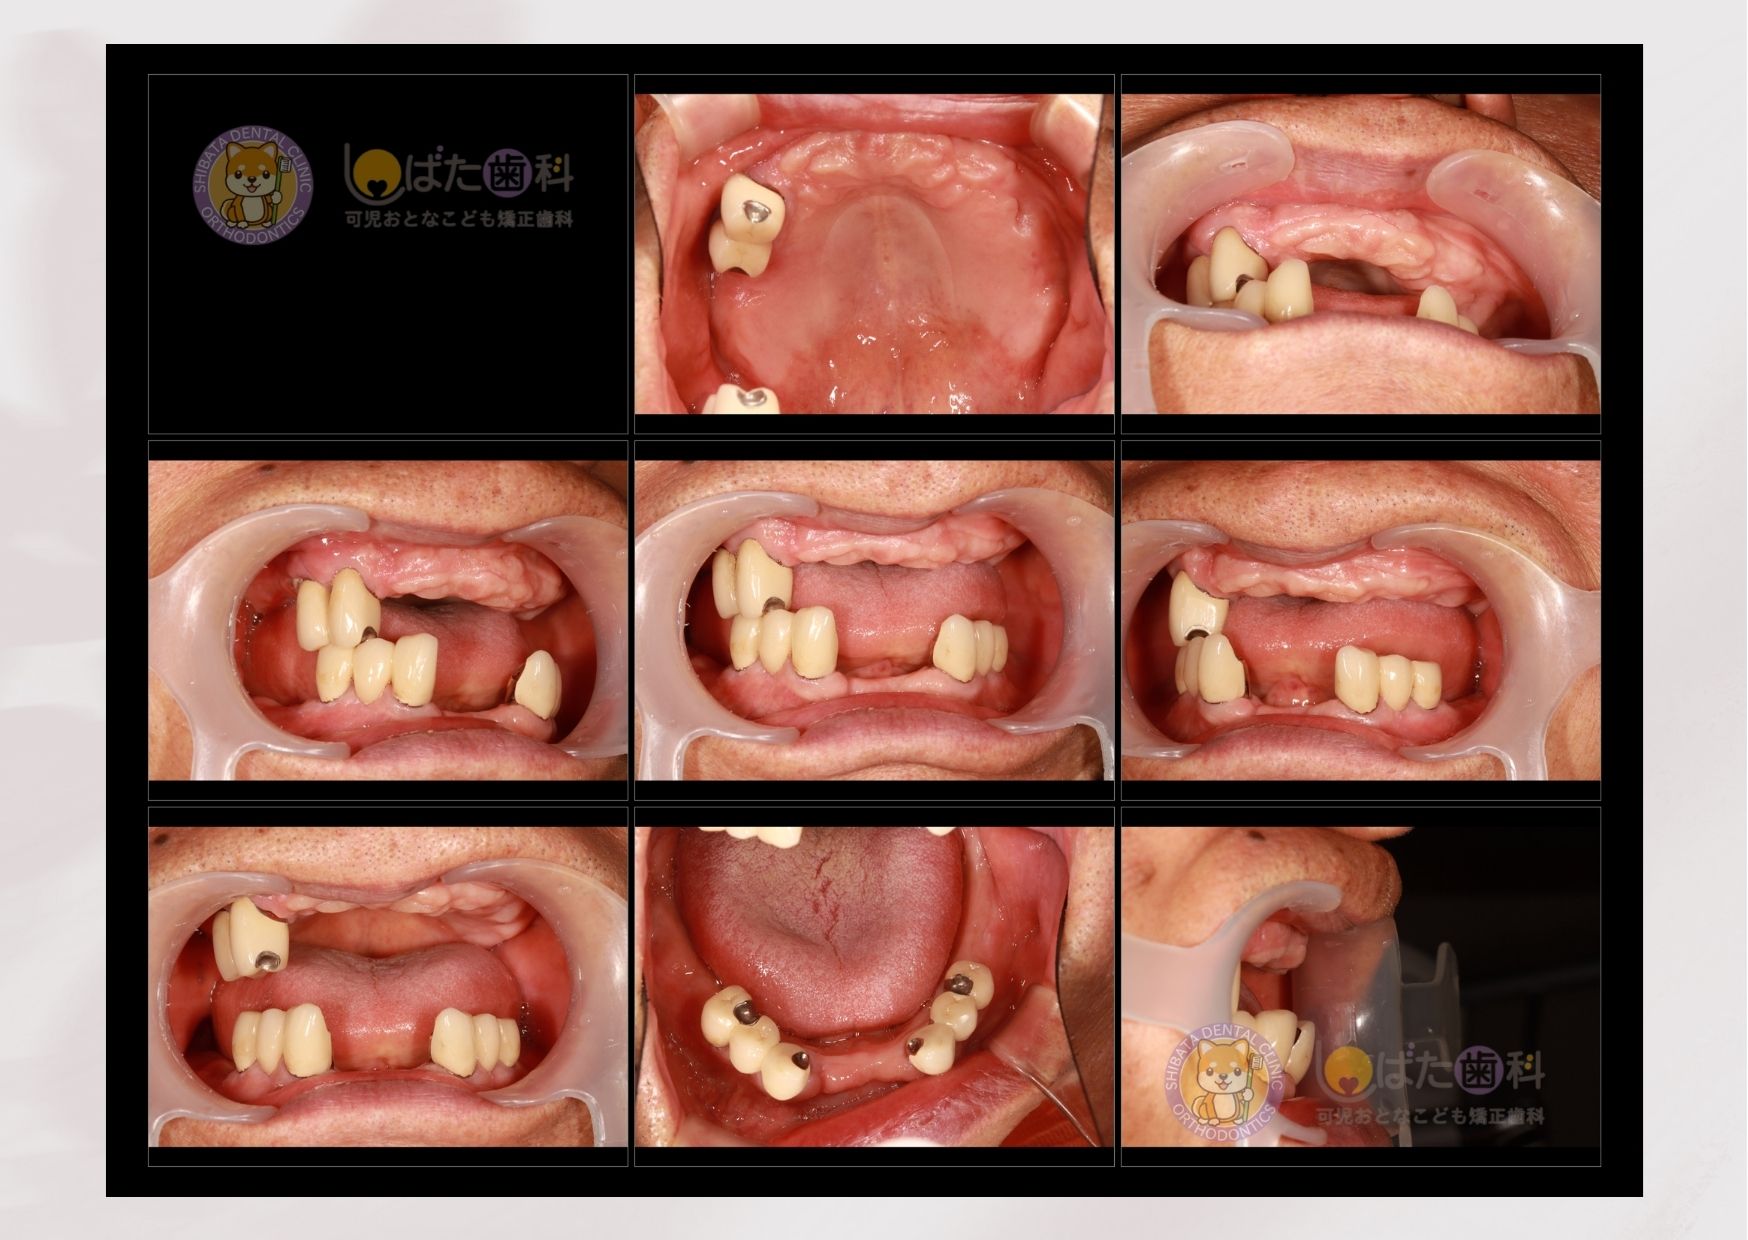

下記は、その一例です。50代女性の患者さんです。

長年原因不明の頭痛に悩まされ、医科に受診ても改善が見られないということでした。きっかけは10年前に入れた銀歯が外れてしまったところからでした。そのまま付け直してもよかったのですが、全顎的な診断をお伝えしたところこの際に全て整えたいということで矯正、インプラントの組み合わせで治療を行いました。

矯正治療の中盤で患者さんからこんな一言が。

「あの、最近、頭痛がなくって。そういえば薬も飲んでないかも」と。

歯並びが改善され、正しい噛み合わせなったことで慢性的に悩んでいたことが改善されたとのことでした。